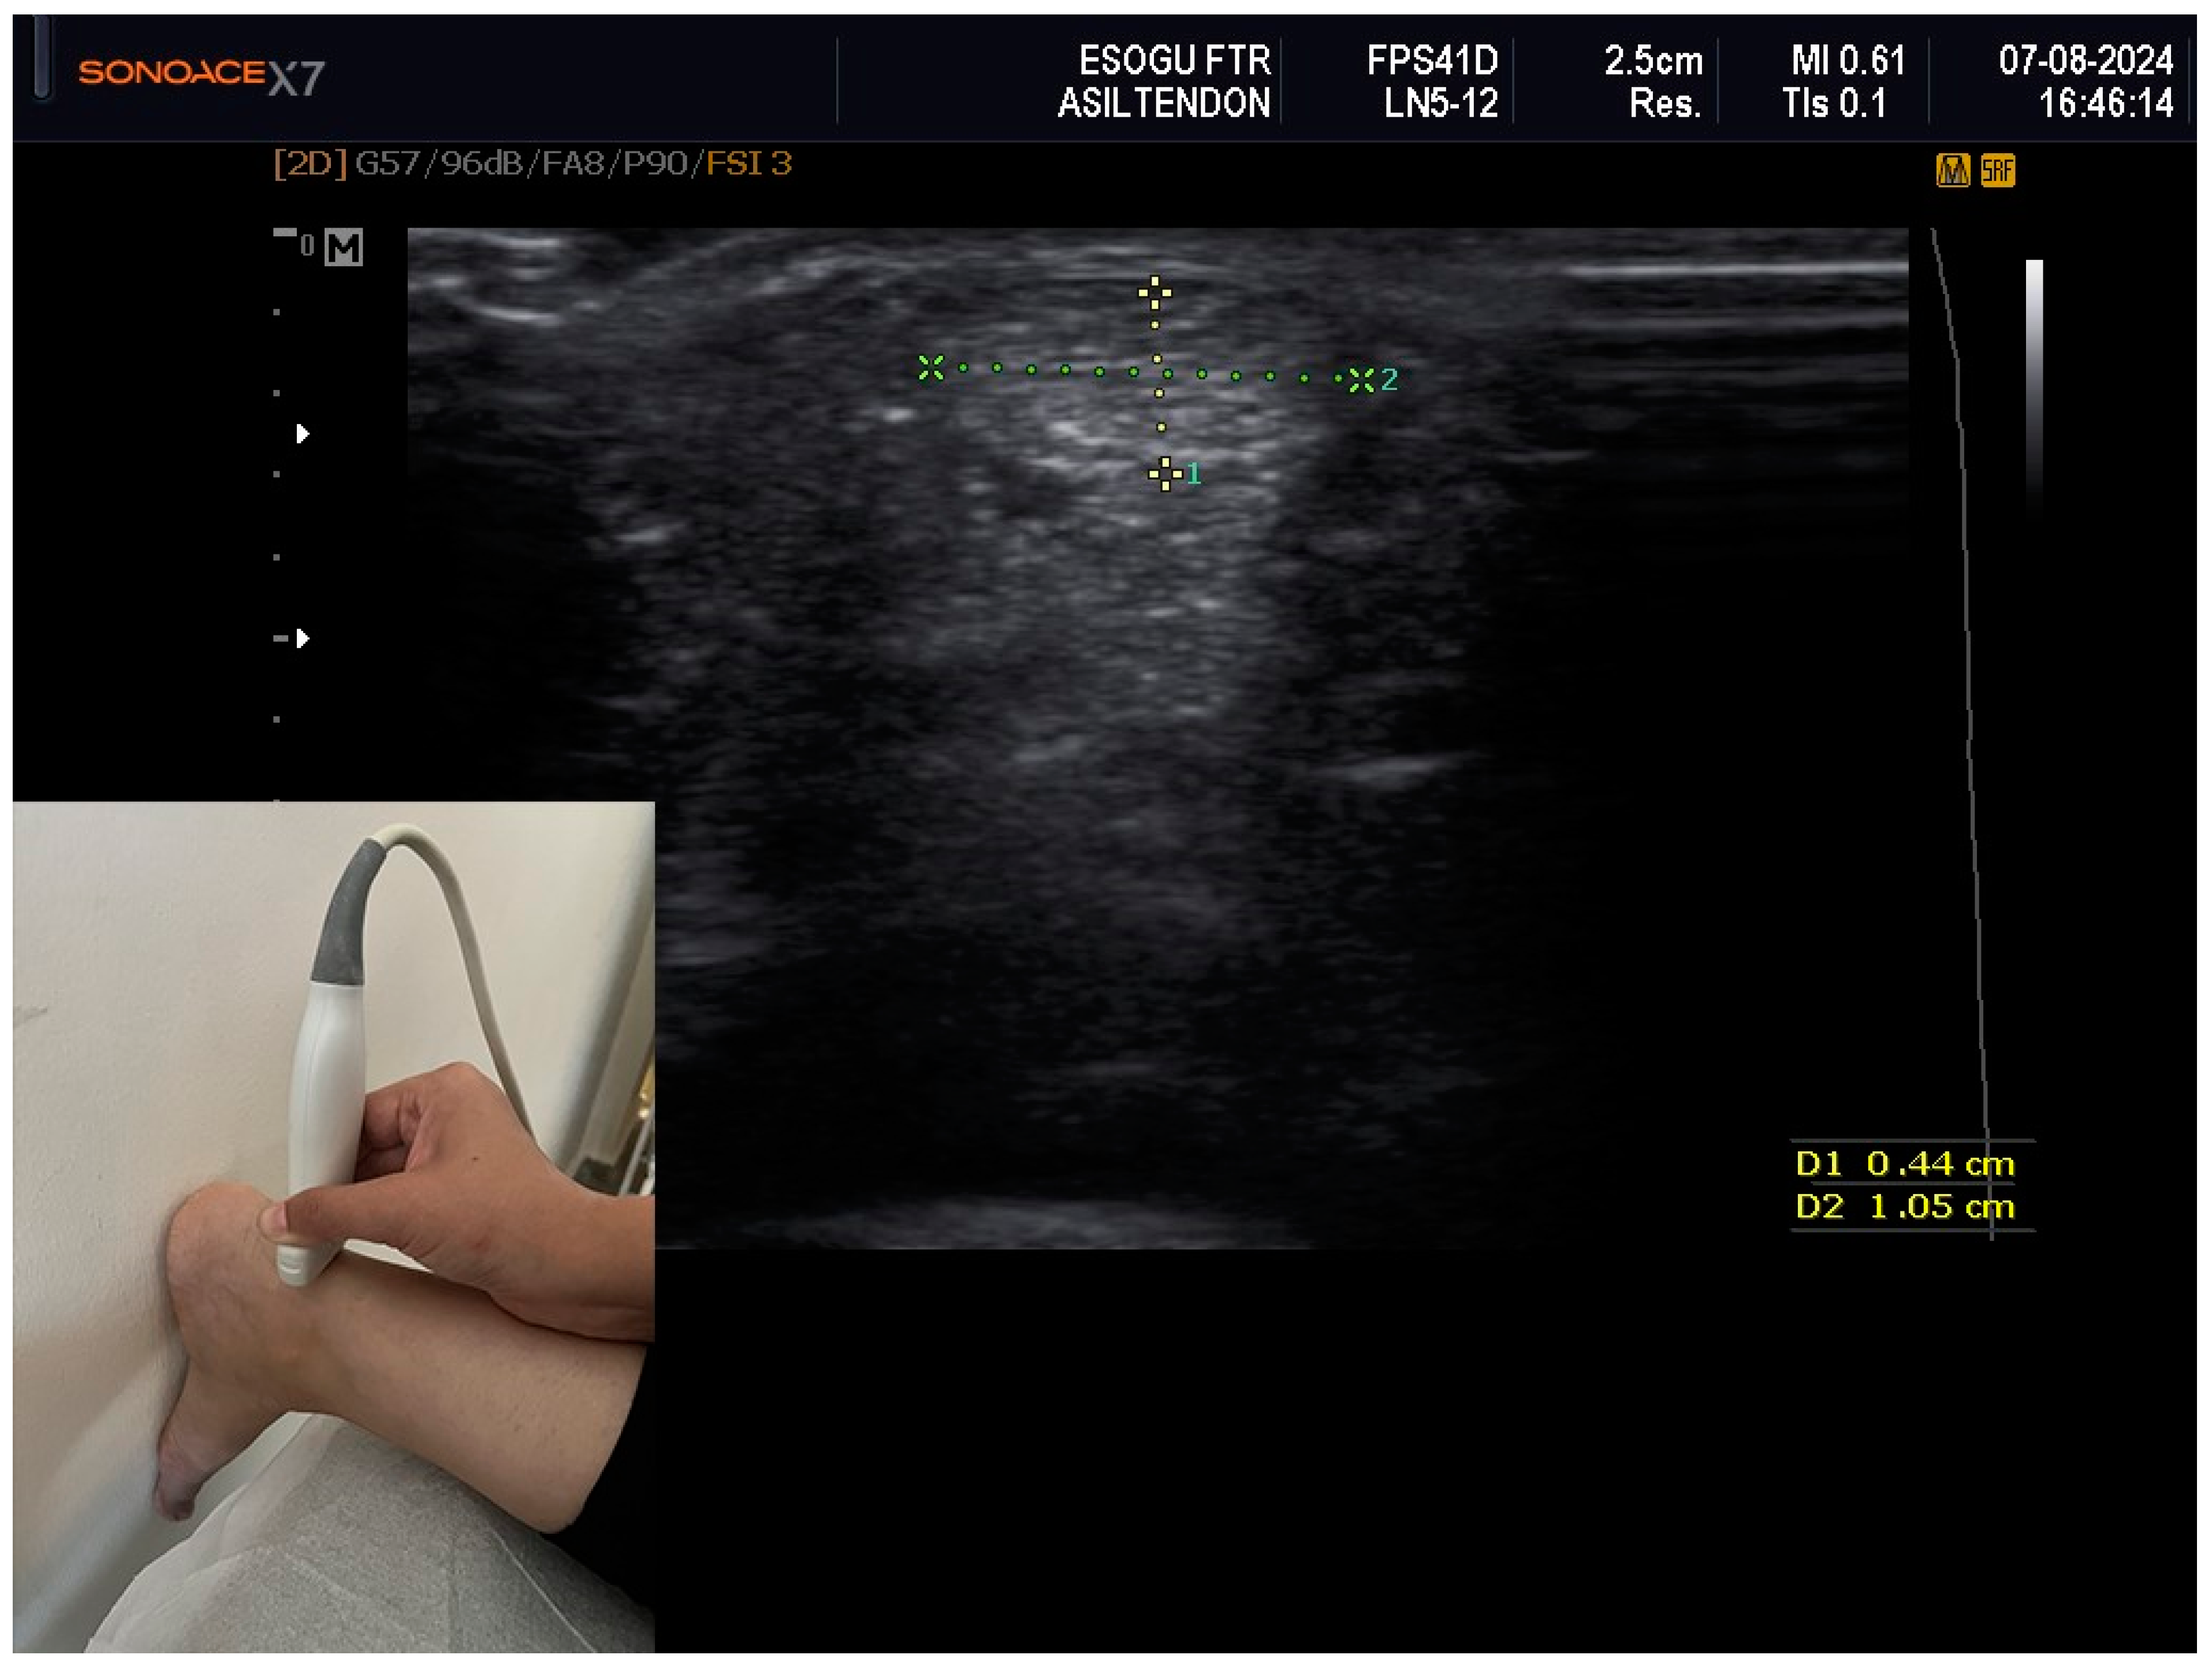

| Ultrasonographic Measurements of Achilles Tendon (mm) | ||||

| Thickness 1 (A-P) (R) | 0.48 ± 0.08 | 0.50 ± 0.08 | 0.48 ± 0.07 | 0.547 |

| Thickness (A-P) (L) | 0.45 (0.40–0.50) | 0.45 (0.41–0.53) | 0.47 (0.43–0.50) | 0.400 |

| Width (M-L) (R) | 1.24 (1.17–1.35) | 1.31 (1.21–1.48) | 1.30 (1.19–1.38) | 0.327 |

| Width 1 (M-L) (L) | 1.28 ± 0.12 | 1.32 ± 0.17 | 1.28 ± 0.16 | 0.586 |

| Area (R) | 0.51 (0.44–0.60) | 0.56 (0.46–0.70) | 0.51 (0.47–0.58) | 0.179 |

| Area 1 (L) | 0.51 ± 0.11 | 0.55 ± 0.13 | 0.53 ± 0.09 | 0.433 |